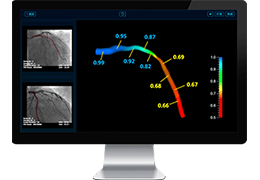

Designed for surgeons, Pro Surgical 3D makes it easy to view patient scans quickly. Pro Surgical 3D facilitates the optimal 3D treatment and assessment workflows based on X-ray CT and MRI scans – and best of all, it’s FREE!

Everyone – including surgeons, patients and their loved ones – benefits from being better informed by the wealth of information buried within CT and MRI scans. Pro Surgical 3D gives surgeons more information to develop optimal treatment plans for patients. It also helps patients and their support group better understand their medical condition and proposed treatment options.

Benefits to surgeons and physicians:

High-quality and fast 3D reconstruction and 3D rendering

Side-by-side comparative assessment for pre- and post-operative scans.